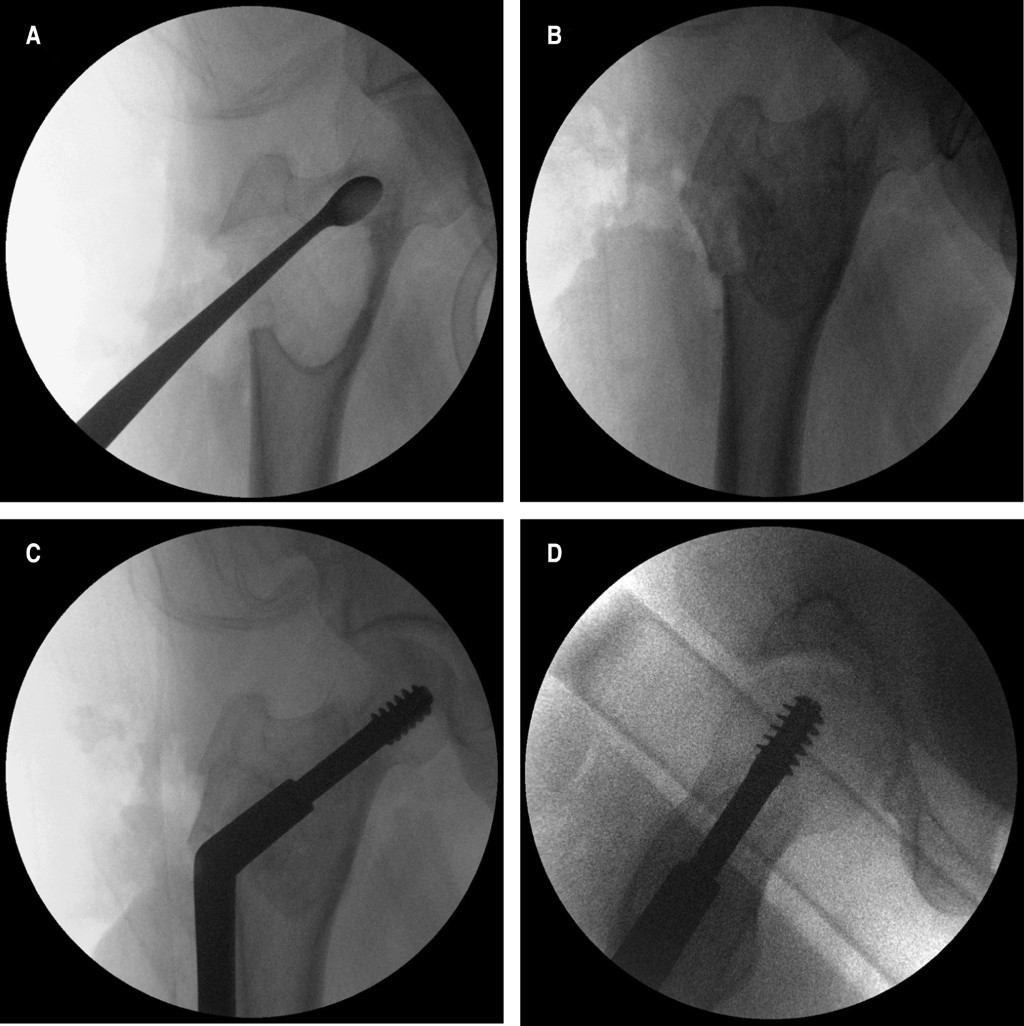

Liposclerosing myxofibroma of the proximal femur: diagnostic and therapeutic controversies. Apropos of 3 clinical cases

Introduction: The bone liposclerosing myxofibrous tumour (LSMFT) is a rare benign fibro-osseous tumor with characteristic clinical-radiological features, although its diagnosis and treatment are controversial. Material and methods: We present three patients, two women and one man, with a mean age of 46 years, diagnosed with LSMFT. The findings of the complementary imaging tests and the treatment performed are presented: observation in two patients and curettage, and the third patient was treated with curettage, grafting and surgical fixation. Results: The first two patients, after 10 and three years of follow-up, respectively, maintain the same symptoms and no progression of the lesion. Conclusions: The diagnosis of LSMFT can be assumed by clinical and imaging data without biopsy. In the absence of signs that suggest malignancy, observation is justified, limiting the surgical indication to symptomatic cases and/or those with risk of pathological fracture.

Figure 2

Figure 3